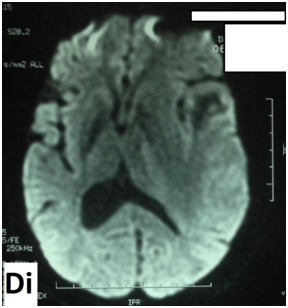

The cerebral MRI showed heterogeneous decreased signal intensity in T1, T2 and Flair-weighted images with variable sizes, surrounded by large area of increased signal intensity in T2 and Flair weighted-images with mass effect on the ipsilateral ventricle (Figure 1). The T1 sequences with intravenous gado injection showed heterogeneous gado enhancement corresponding to the area withT2 and Flair decreased signal intensity (Figure 2). This pattern corresponds to the “swiss cheese” and “soap bubble” aspect. The diffusion weited image showed increased ADC with increased water mobility in left temporal lobe (Figure 3). The radiological conclusion was temporal radionecrosis with large vasogenic edema, or the differential diagnosis of cerebral metastasis of the primary nasopharyngeal carcinoma. Thus, a spectroscopy was performed, and showed decreased peak of N-Acetyl-Aspartate (NAA) and Creatinine (Cr), with normal choline peak. The diagnosis of temporal radio necrosis was established. The patient was proposed to hyperbaric oxygen. His Oto-rhino-laryngeal examination was normal, as much s the chest X-ray. So a daily 45 minutes session, were performed for 10 successive days, associated to bolus of methylprednisolone (240mg/d for 10 days), anti-platelet agent (aspirin 160mg/d). The evolution was favorable, with regression of vestibular signs, improvement of memory and phasic troubles with recovering four lost points in MoCA score. The cerebral CT scan showed partial regression of the gliosis with no more mass effect on the ipsilateral ventricle (Figure 4).

Figure 1 Cerebral MRI in coronal T2-weighted image (A) and axial Flair-weighted image, showing heterogeneous decreasing signal intensity with variable sizes corresponding to necrosis area, surrounded by increased signal intensity corresponding to peri lesional edema with mass effect on the ipsilateral ventricle.